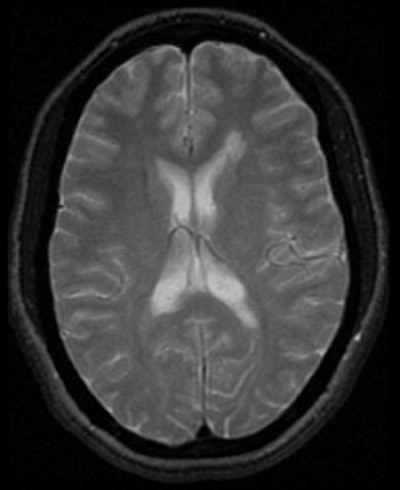

![]() |

| T2-weighted images of 29-year-old woman illustrate centrifugal method of interrogating normal-appearing white matter (WM) adjacent to MS plaques. Axial T2-weighted MR image shows demyelinating plaque adjacent to anterior horn of left lateral ventricle. Kealey SM, Kim Y, Provenzale JM, "Redefinition of Multiple Sclerosis Plaque Size Using Diffusion Tensor MRI," (AJR 2004;183: 497-503). |